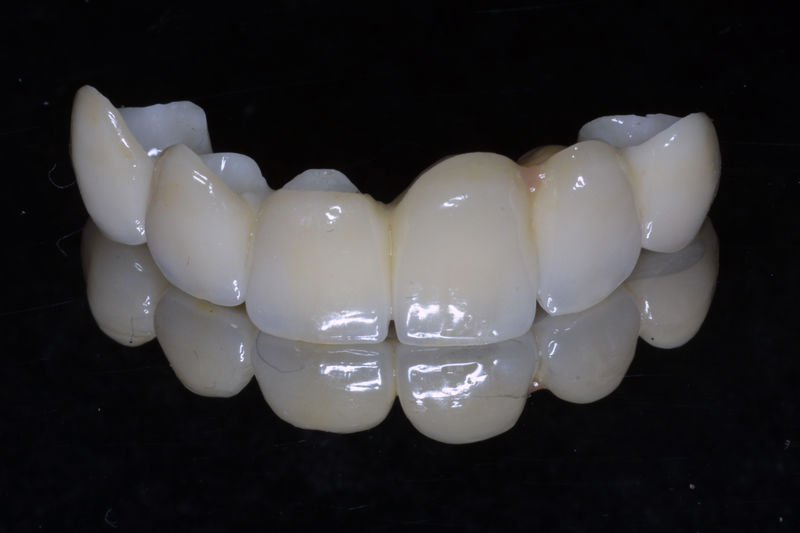

Restauraciones fabricadas en el laboratorio con materiales estéticos, los cuales cubren de manera total dientes anteriores y posteriores. Se utilizan primariamente para restaurar dientes con caries, fracturas y/o defectos amplios, así como soportes de puentes. Para poder enviar el caso al laboratorio se toman impresiones utilizando materiales de impresión o técnicas modernas digitales.

Restauraciones fabricadas en el laboratorio con materiales estéticos, los cuales se usan para reemplazar dientes ausentes usando coronas como soporte. Para poder enviar el caso al laboratorio se toman impresiones utilizando materiales de impresión o técnicas modernas digitales.

Amplia gama de tratamientos para mejorar la apariencia de la sonrisa, corrigiendo el color, la forma, el tamaño, la alineación y la posición de los dientes. Los procedimientos más comunes y solicitados incluyen el blanqueamiento dental, las carillas y coronas, así como las resinas.